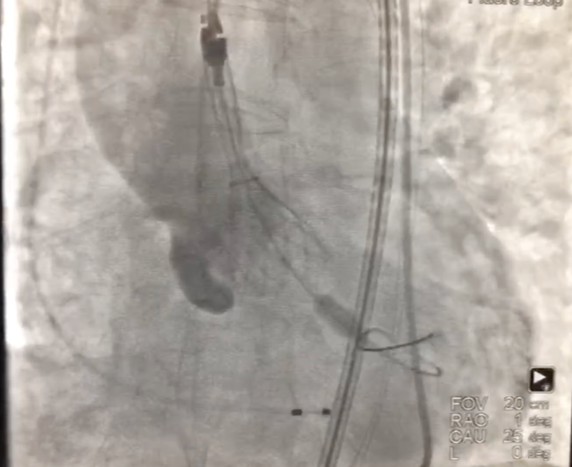

04

术后心电监护未见传导阻滞,心超提示人工主动脉瓣工作良好,瓣叶启闭正常,主动脉瓣峰值流速2 m/s,平均跨瓣压差6 mmHg,轻度瓣周漏。

图片

主动脉根部造影示瓣膜位置合适(深度2 mm),轻度瓣周漏。遂释放瓣膜,撤回脑保护装置,手术圆满成功